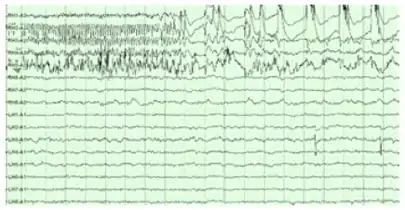

Electroencephalography

The hippocampus shows two major "modes" of activity, each associated with a distinct pattern of neural population activity and waves of electrical activity as measured by an electroencephalogram (EEG). These modes are named after the EEG patterns associated with them: theta and large irregular activity (LIA). The main characteristics described below are for the rat, which is the animal most extensively studied.[79]

The theta mode appears during states of active, alert behavior (especially locomotion), and also during REM (dreaming) sleep.[80] In the theta mode, the EEG is dominated by large regular waves with a frequency range of 6 to 9 Hz, and the main groups of hippocampal neurons (pyramidal cells and granule cells) show sparse population activity, which means that in any short time interval, the great majority of cells are silent, while the small remaining fraction fire at relatively high rates, up to 50 spikes in one second for the most active of them. An active cell typically stays active for half a second to a few seconds. As the rat behaves, the active cells fall silent and new cells become active, but the overall percentage of active cells remains more or less constant. In many situations, cell activity is determined largely by the spatial location of the animal, but other behavioral variables also clearly influence it.

The LIA mode appears during slow-wave (non-dreaming) sleep, and also during states of waking immobility such as resting or eating.[80] In the LIA mode, the EEG is dominated by sharp waves that are randomly timed large deflections of the EEG signal lasting for 25–50 milliseconds. Sharp waves are frequently generated in sets, with sets containing up to 5 or more individual sharp waves and lasting up to 500 ms. The spiking activity of neurons within the hippocampus is highly correlated with sharp wave activity. Most neurons decrease their firing rate between sharp waves; however, during a sharp wave, there is a dramatic increase in firing rate in up to 10% of the hippocampal population